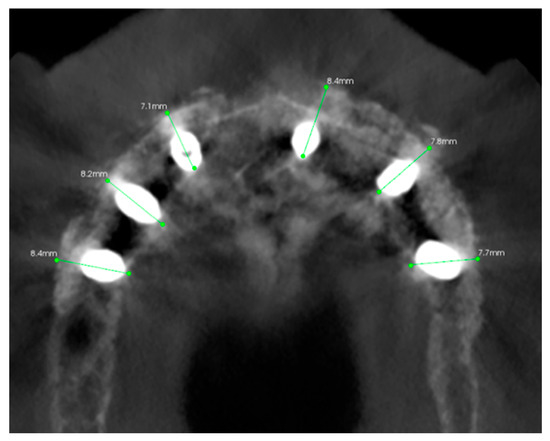

3.2. Surgical Guide Accuracy